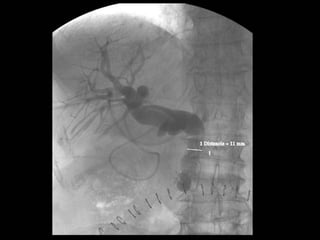

• #17 DISMINUCION DE CALIBRE DEL COLEDOCO DISTAL CON DILATACION DE LA VIA BILIAR INTRA Y EXTRAHEPÁTICA EN RELACIÓN A EDEMA DE PAPILA O A ESPASMO DE ESFINTER DE ODDI.

• #18 Imagen por fluoroscopia evidencia imagen radiolucides de via biliar con dilatación de via intra y extra hepatica